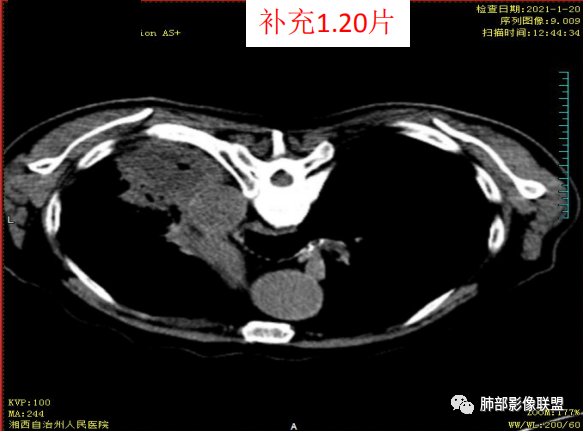

抗炎3周洞臂缩小

18号复查肺窗空洞显示不清,20号用了俯卧位扫描,液体向下流动空洞又显示出来了。

当时就觉得这个强化像个肿瘤,但时复查洞明确变小了,就考虑感染了,不过没想到是腺癌

大雄: 空洞短期变化,这个确实有迷惑性,也遇到过几例,这个病例应该是合并感染了

2.患者发热,中性粒细胞等炎性指标轻度升高,C-反应蛋白高,短期内双肺病灶吸收明显,吸收部分较符合普通感染性病灶,也可以因部分肺泡积血有所吸收。